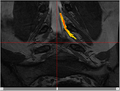

We are developing a nerve segmentation algorithm for the automatic isolation of nerves and nerve ganglia inside the spinal sack and out through the vertebrae in new MR Myelography images.

Currently we use a particle-filter tracking approach for segmenting the nerves. The algorithm is given a seed point, preferably somewhere in the spine. The particles are tubes following Bézier curves (and hence forming a B-spline track). To compute the likelihood of each sample we are experimenting with measures that use image intensity and gradients within the patch. Correct partial volume estimates are important in the measure as well.

• See Figures 4-6